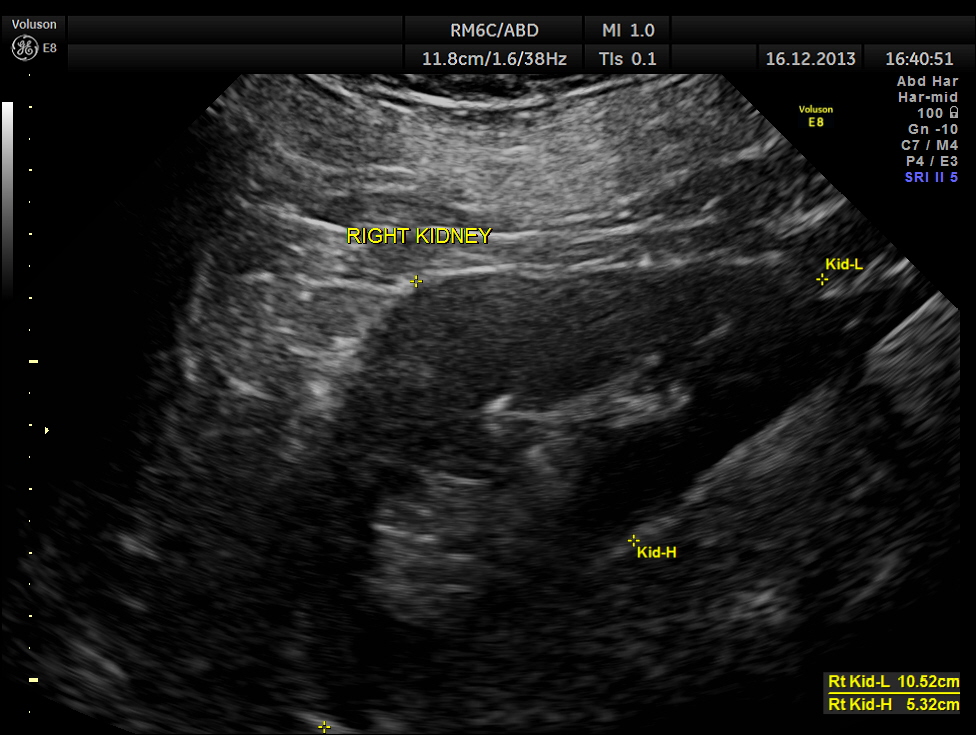

He also had mild prostatomegaly.